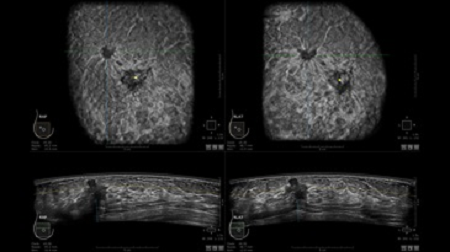

GE INVENIA ABUS – это современный УЗИ аппарат, который создан для точной и эффективной диагностики сканирования с высокой плотностью молочных желез. Выявляемость патологий раковых и предраковых стадий заболевания составляет 55%, что в конечном счете позволяет ставить врачу точные и своевременные диагнозы. Традиционные методы использования маммографии не показывают такой выявляемости, ограничиваясь лишь 3-38%.

УЗИ-аппарат GE INVENIA ABUS позволяет проводить максимально операторонезависимые процедуры, что значительно снижает риск неправильной постановки диагноза и сопутствующие издержки на обработку информации. Система готовит отчет в течение 3-х минут после сканирования, это безусловное преимущество по сравнению с обычным УЗИ сканером.

• датчик с изогнутой апертурой для качественного исследования

• сканирование одной грудной железы в трех проекциях не более 60 сек.;

• обработка результатов за три минуты.

• Отображение объемных 3D ультразвуковых изображений, которые состоят из традиционных поперечных и воссозданных коронарных и сагиттальных проекций

• Стандартизованная ориентация изображения: «толстый срез» в коронарной плоскости; поперечная; сагиттальная плоскость; радиальный и антирадиальный поворот изображения; просмотр исключительно области интереса

• Одновременный просмотр двух изображений для сопоставления в коронарной плоскости